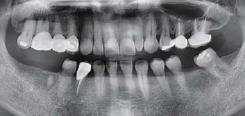

술 전 파노라마

술 후 파노라마